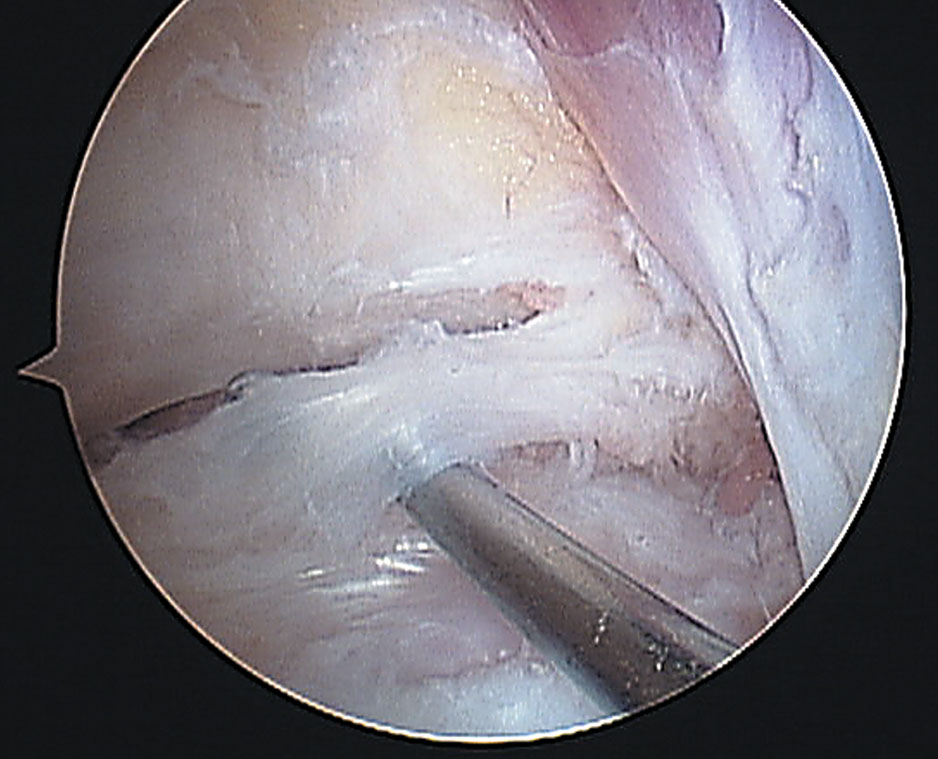

Luego nos encontramos el complejo ligamentario posterior de tobillo compuesto por el ligamento tibiofibular posterior y el ligamento talofibular posterior (Fig. 3).

Figura 3: Preparado anatómico de 1) Ligamento tibiofibular posterior

y 2) Ligamento talofibular posterior.